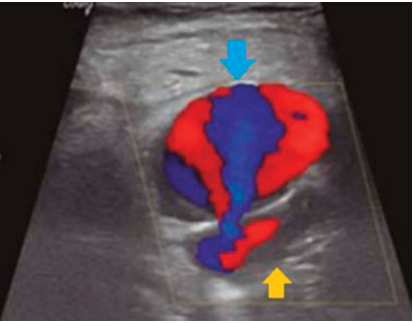

De nuestra serie de casos (n ¼ 228), solo se encontraron complicaciones en el 16,6%: hemorragias subaracnoideas secundarias a perforación (n ¼ 2) (►Fig. 1), hemorragia gangliobasal (n ¼ 1) (►Fig. 2), vasoespasmo (n ¼ 1), disección (n ¼ 1) (►Fig. 3), embolias (n ¼ 31) y pseudoaneurismas (n ¼ 2) (►Fig. 4) en el sitio de la punción. Cuando se detectó oclusión intracraneal (►Fig. 5), tras la trombectomía, dentro del grupo de las embolias, solo el 16,1% se presentaron hacia nuevo territorio vascular (arteria cerebral anterior) (►Fig. 6) o embolias distales. Debido al bajo número de complicaciones, se realizó un análisis mediante Fisher que da un resultado no significativo (►Tabla 3). Las hemorragias fueron subaracnoideas detectadas durante las trombectomías como la extravasación activa del contraste y corroborada mediante tomografía computada (TC) al finalizar el procedimiento. El vasoespasmo que se presentó fue moderado en arteria cerebral media izquierda que cedió tras la infusión intra-arterial de 0,2 mg nimodipino.

Tras hematoma púlsatil en el sitio de la punción femoral se realiza ultrasonido doppler que confirma la presencia de pseudoaneurisma (flecha azul), de la arteria femoral parenteral (flecha amarilla).

Dentro del grupo de embolias distales, el 61% registraron 1 embolia, el 22% registraron 2 embolias, el 3% registró 3 embolias y el 14% registraron más de 3 embolias (►Gráfico 1). Los 2 pseudoaneurismas fueron femorales, ambos pacientes habían recibido r-TPA, 1 recibía anticoagulación por fibrilación auricular y el de mayor tamaño no superaba los 30 mm de diámetro mayor, ambos tratados mediante inyección ecoguiada de trombina.